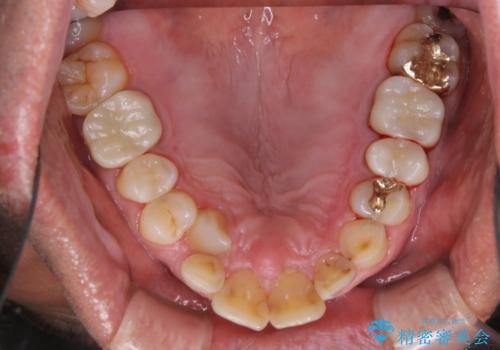

歯科衛生士による専門的なクリーニングPMTC(保険外治療)60分コースを行いました。

専門的な機械・材料を使用して徹底的に汚れを取り除きました。

染め出しをして、磨き残しの確認・ブラッシング指導も行いました。